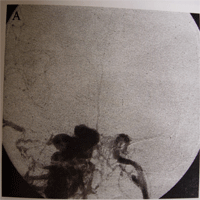

1、腦血管造影間接型頸動脈海綿竇瘺腦血管造影檢查的目的是確定瘺口的位置,供血動脈,靜脈引流形式,有無頸外動脈系統與頸內動脈系統和椎動脈系統的“危險吻合”等。腦血管造影檢查的內容包括患側頸內動脈的選擇造影,患側的椎動脈,頜內動脈,咽升動脈造影和對側頸內動脈和頸外動脈的選擇造影。微導管超選擇造影可進一步了解各供血動脈的供血情況。正常情況下,海綿竇接受眼上、下靜脈和蝶頂竇的引流,再經岩上、下竇引流到橫-乙狀竇交界處和頸靜脈球。兩側的海綿竇經海綿間竇相交通。在CCF存在的情況下,海綿竇內壓力增高,血流方向發生改變:經眼上靜脈逆流入角靜脈和面靜脈,經海綿間竇注入對側海綿竇,以及逆流入蝶頂竇等。此類頸動脈海綿竇瘺的供血情況通常非常複雜。在經動脈途徑栓塞治療前,必須仔細研究腦血管造影,特別注意有無“危險吻合”的存在。頸總動脈分叉處的情況也是腦血管造影要觀察的重要內容。如果該處有動脈粥樣硬化斑塊,則禁止採用壓迫頸總動脈的方法治療間接型頸動脈海綿竇瘺。